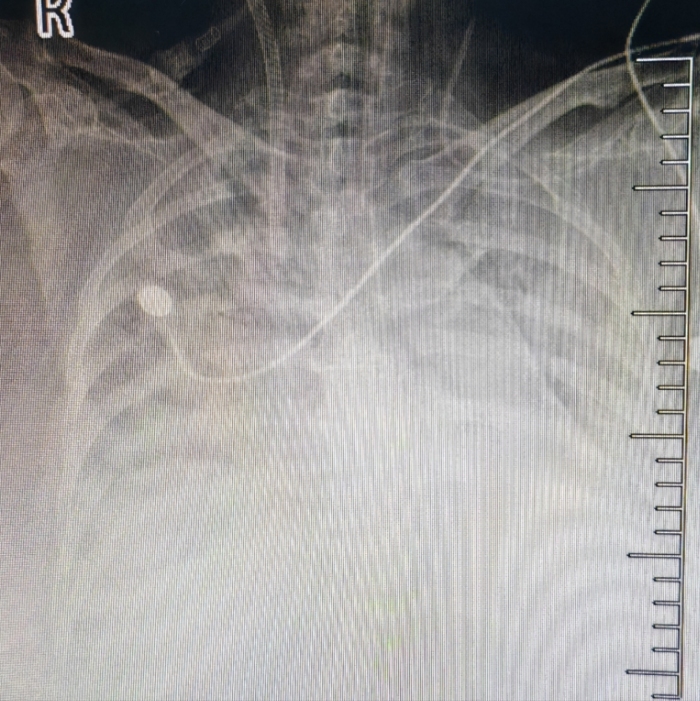

今年1月,赵阿姨因“感冒”症状到自治区南溪山医院呼吸与危重症医学科二病区就诊。经检测,她被确诊为甲型流感病毒感染。然而,病情迅速恶化,她的肺部出现严重感染,形成“大白肺”,导致急性呼吸衰竭,血氧饱和度骤降至66%,氧合指数仅为39mmHg,生命危在旦夕。

患者胸片“大白肺”

面对如此凶险的病情,呼吸与危重症医学科二病区主任屈东明立即联系综合重症医学科主任韦妍飞进行会诊。经评估,赵阿姨被诊断为:急性呼吸窘迫综合征(重度)、重症肺炎、甲型流感病毒感染(重症)、I型呼吸衰竭。此时,常规呼吸机治疗已无法维持她的生命,必须采取更积极的救治手段。